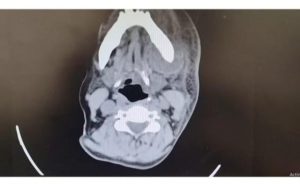

وأشار إلى أن الفحوص الطبية أظهرت وجود خراج في المساحات التشريحية الحساسة من الجانب الأيسر للفك السفلي، وامتداده إلى المنطقة الجناحية الفكية، والمساحة المجاورة للبلعوم، وهي مناطق قريبة من مجرى الهواء الحيوي، مما استدعى تحركًا طبيًا عاجلًا.